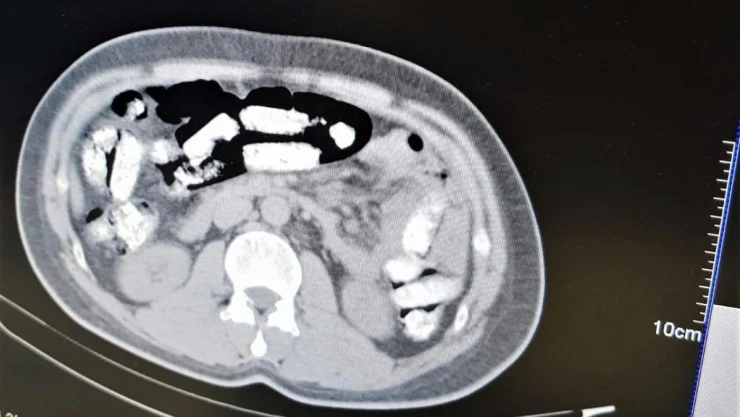

Erzincan İl Emniyet Müdürlüğü Narkotik Suçlarla Mücadele Şube Müdürlüğü ekiplerince uyuşturucu madde kuryeliği yapan şahıslara yönelik İran otobüsleri üzerinde yapılan uygulamada; İran otobüsünde yolculuk yapan Abdulmennan S. isimli İran uyruklu kişinin yutma yöntemiyle uyuşturucu taşıdığı değerlendirilmesi üzerine, Erzincan Mengücek Gazi Eğitim ve Araştırma Hastanesinde zanlının bedeninden 106 fişek halinde toplamda 1 kilo 198 gram Afyon Sakızı ele geçirildi. Abdulmennan S. hakkında TCK 188 suçundan yapılan tahkikat sonrası sevk edildiği mahkemece tutuklanarak cezaevine teslim gönderildi.